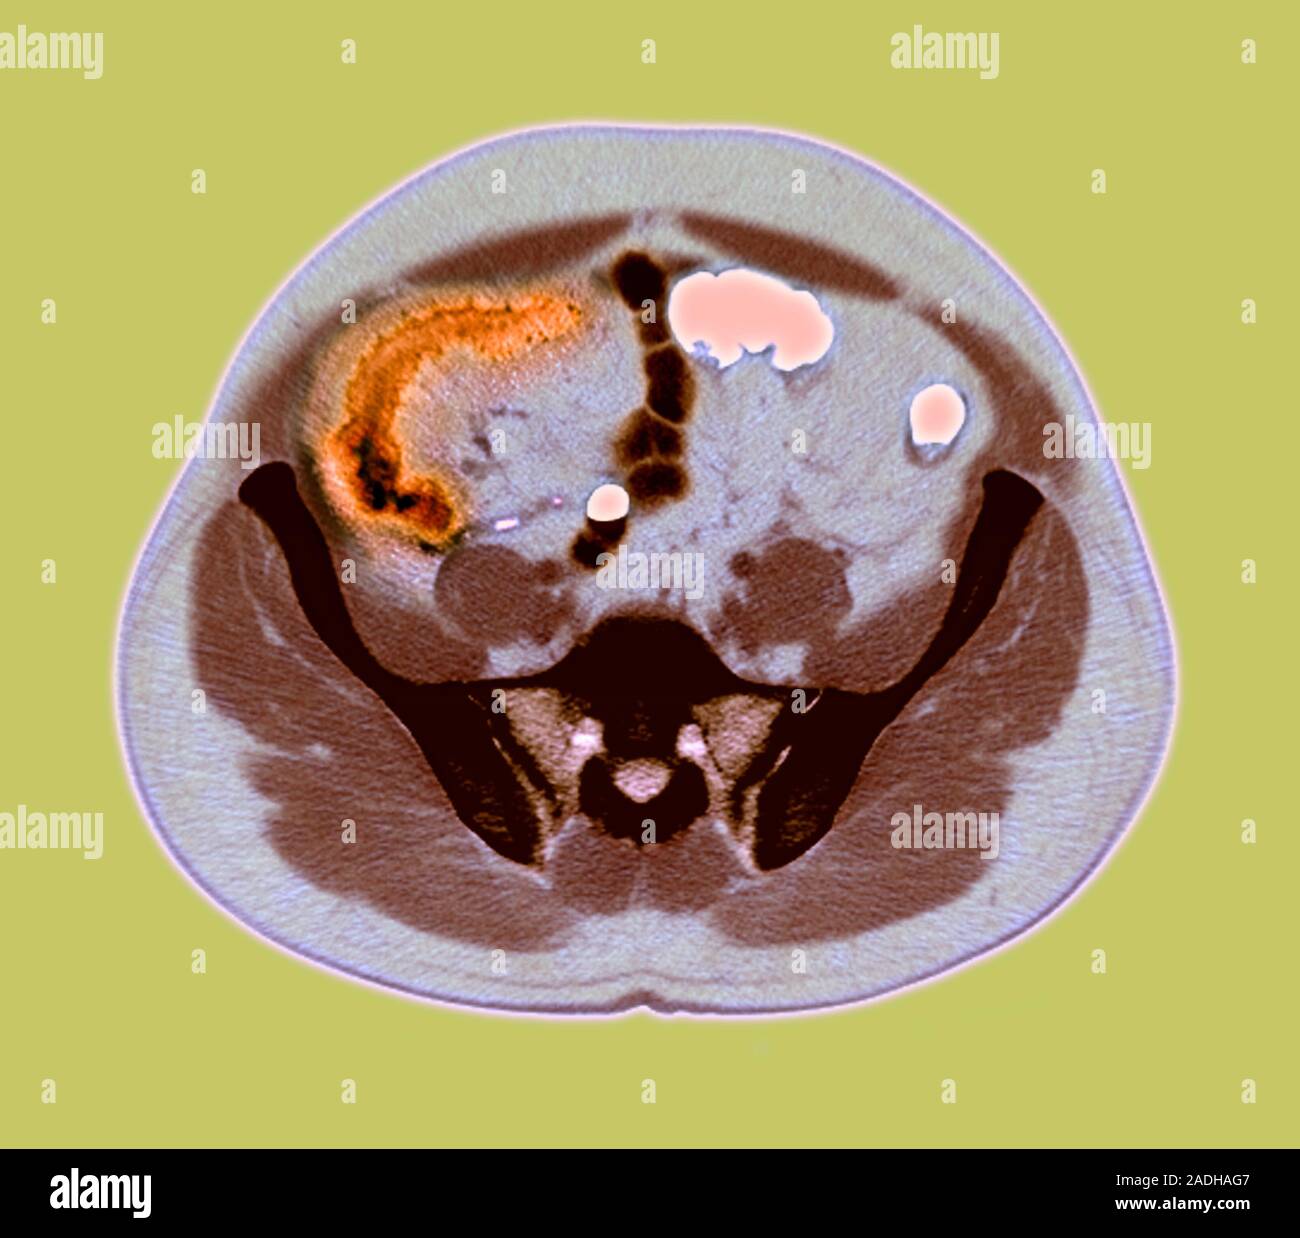

Crohn disease. CT scan obtained with oral and intravenous contrast Can An Mri Scan Detect Crohn Disease There’s no single diagnostic test for crohn’s disease. You may also undergo flexible sigmoidoscopy, colonoscopy, body ct, body mri, mr enterography, upper gi, small bowel follow. New and emerging roles of mri in inflammatory bowel disease. A systematic approach is presented to grade disease. In addition, mri enterography and enteroclysis has allowed detection of small bowel crohn disease, similar to. Can An Mri Scan Detect Crohn Disease.